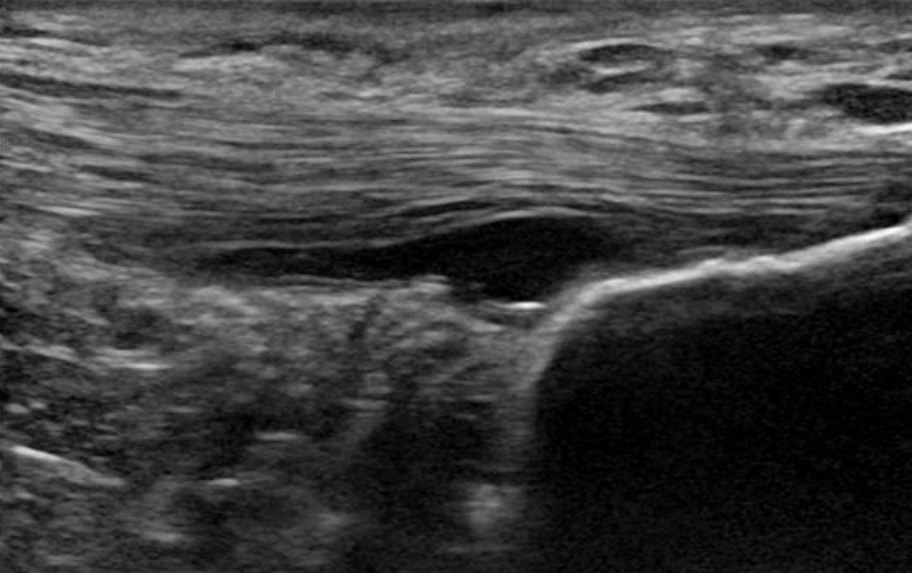

1. Niciceptivni vzrok bolečine v kitah ni znan. Patologija, vidna na slikovni sliki, ni vzrok bolečine. Vaskularnost ni vir bolečine, temveč le pokazatelj degeneracije tetive. Poleg tega čutilnih živcev ni globoko v tetivi, temveč na periferiji okoli tetive. Živci, ki se vraščajo v patološko tetivo, so simpatični živci in ne senzorični. Nenazadnje je centralna senzibilizacija pri patologiji spodnjih okončin verjetno manjši problem kot pri patologiji zgornjih okončin(Plinsinga et al. 2015, Plinsinga et al. 2018).

2. Degenerativne patologije tetiv ne moremo popraviti/zdraviti. Z drugimi besedami, degenerirane kite ne more popraviti ali pozdraviti nobena operacija, nobena terapija z udarnimi valovi, nobene injekcije in niti vadba. Docking et al. (2019) menijo, da so lahko celice v degenerativnem delu tetive premalo stimulirane in ne prejmejo potrebnih mehanskih dražljajev za remodelacijo, kar pojasnjuje omejeno sposobnost patološke tetive za remodelacijo in normalizacijo. Čeprav se vam zdi, da je to slaba novica, je dobra novica ta, da ni nujna. Študija, ki so jo opravili Tsehaie in sod. (2017) so pokazali, da 24 tednov ekscentričnih vaj za Ahilovo tetivo ni povzročilo sprememb zunaj meja zaznavnih sprememb v tetivi, kljub temu pa se je stanje bolnikov izboljšalo. Ugotovili so tudi, da je o MRI parameter na začetku napovedoval spremembo simptomov, tako da tudi če je vaša MRI videti grozno, to ni pomembno.

6. Patološka tetiva ima bolj dobro strukturo kot normalna tetiva(Docking et al. 2015). To pomeni, da lahko te kite obremenimo, saj imamo veliko dobrega tkiva. Terapije pri patologiji tetiv niso potrebne, saj strukture patološkega dela tako ali tako ne moremo spremeniti. Zato so Docking in njegovi sodelavci oblikovali citat "Zdravite krof, ne luknje" - z drugimi besedami, osredotočite se na zdravo strukturo in ne na patološki del.

Patološka tetiva ima bolj dobro strukturo kot normalna tetiva (Docking et al. 2015)